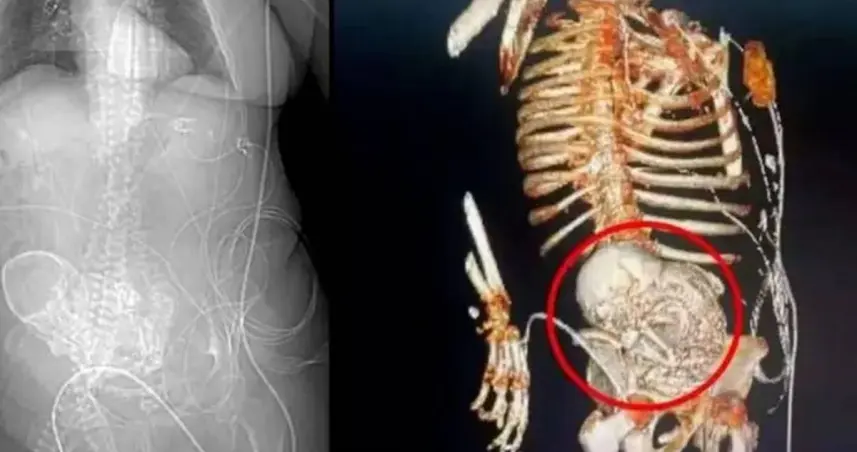

De acuerdo a los médicos, la brasileña de 81 años habría quedado embarazada hace décadas, cuando tenía entre 40 y 50 años, pero el óvulo se fertilizó fuera del útero, por lo que deriva en la muerte del feto y su posterior calcificación.

La mujer, que toda su vida se rehusó a visitar médicos y optar a la medicina natural, solo se enteró de que llevaba en su cuerpo un feto calcificado luego de que sufrió una caída y para atender los malestares le practicaron una tomografía.

Tras hacer el extraño descubrimiento, los médicos decidieron realizarle una cirugía, pues a consecuencia de la caída que sufrió más la presencia del feto calcificado se le había desarrollado una grave infección.